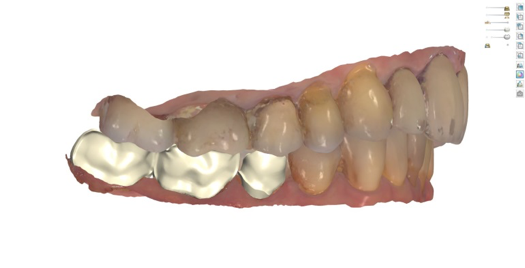

Fig 10. Titanium abutment proposal.

Figure 10

Fig 11. Final crown proposal.

Figure 11

After 4 months of healing and integration of the bone around the implant, the digital workflow was initiated to develop the abutment and treatment plan. Another analog impression was made with an impression post and polyvinyl impression. The laboratory scanned the impression and digitized it to create the emergence profile of the milled titanium abutment and the final restoration (Figure 10 and Figure 11). The patient had a considerably thick soft-tissue profile, allowing a milled titanium abutment. The decision to use a titanium abutment was based on the patient's occlusion and propensity to fracture teeth or restorations. The virtual model was gray because the scanner does not recognize the color of the analog impression. The virtual final abutment and crown were approved and fabrication completed. The final restoration met the patient's esthetic values and his ability to function (Figure 12 and Figure 13).